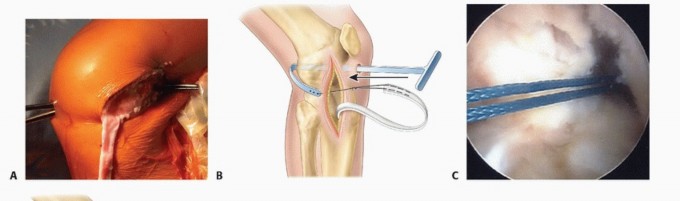

The anterior and posterior borders of the iliotibial band are incised and the incisions carried proximally under the skin using curved meniscotomes ( TECH FIG 1A ).

Dissection is performed distally to separate the iliotibial band from the joint capsule and from the lateral patellar retinaculum ( TECH FIG 1B ).

The iliotibial band is left attached distally at the tubercle of Gerdy ( TECH FIG 1C ).

The free proximal end of the iliotibial band is tubularized with a no. 5 Ethibond whipstitch and wrapped in a moist sponge until needed later. -

The free end of the iliotibial band graft is brought through the over-the-top position using a full-length clamp ( TECH FIG 2A )

or a two-incision rear-entry guide (

TECH FIG 2B

) and out the anteromedial portal (

TECH FIG 2C,D

).

TECH FIG 1 • Harvest of iliotibial band graft for physeal-sparing ACL reconstruction. The anterior and posterior aspects of the iliotibial band are identified through a laterally based incision at the knee. A. A meniscotome or an open tendon stripper is then used to harvest the proximal aspect of the graft. B. The graft is then freed distally. C. The free proximal aspect of the graft is tubularized and left attached distally to the tubercle of Gerdy. (A,B: From Kocher MS, Weiss JM. ACL reconstruction in the skeletally

immature patient. In: Tolo VT, Scaggs DL, eds. Master Techniques in Orthopaedic Surgery: Pediatrics. Philadelphia: Lippincott Williams & Wilkins, 2008:277-287.)